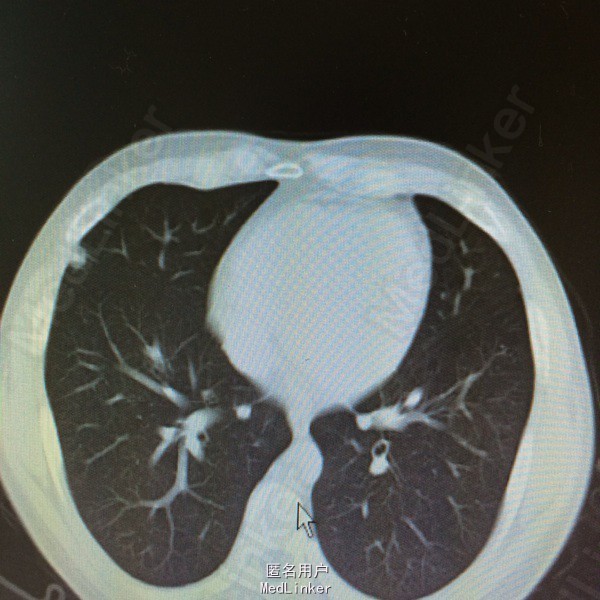

患者因“鼻咽癌放疗后2年余,双肺多发转移治疗后复发2周”入院。详见图片

查体一般可,生命体征平稳,双颈部等浅表未及明显肿大淋巴结,2015.9.15复查ct提示两肺多发转移瘤,较前增多增大。

鼻咽癌肺转移,拟予全身化疗

患者鼻咽癌肺多发转移,目前鼻咽部及双颈部CR,双肺多发转移后予全身化疗及全肺姑息性放疗,放疗后全肺缓解期8个月,未见肺炎。放疗后复发予全身化疗,化疗后缓解期约3个月,现再次复发,但患者血象不宜全身化疗,讨论治疗方案